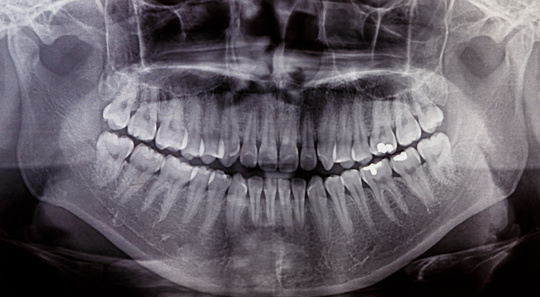

智歯(ちし)、第3大臼歯のこと。

通称:親知らず といい、親から独立する頃に生えてくる歯。

6歳に生える第一大臼歯(6番、6歳臼歯)、12歳ごろ生える第2大臼歯(7番、12歳臼歯)に続いて、その奥に生えてくる大臼歯(8番)です。

上下左右4本ある人が大多数。 1本も無い人、1本しか無い人、上下片っぽだけある人もいます。